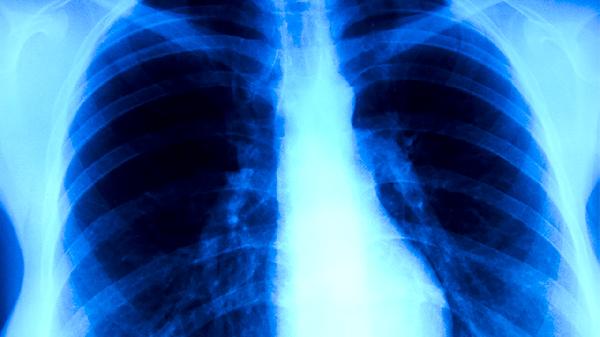

必须明确,重症肺炎病情凶险,变化迅速,其核心治疗必须依赖于现代医学。这包括根据病原学检查结果使用敏感的抗生素或抗病毒药物,对于出现呼吸衰竭的患者及时进行氧疗或无创、有创机械通气,维持循环稳定,以及必要的营养支持等。这些是挽救生命的关键措施,中医药不能替代。任何中医药的介入都应在患者病情相对稳定、且经西医主管医生同意的前提下,由经验丰富的中医师进行辨证施治,确保治疗的安全性与协同性,避免因不当用药延误或干扰核心治疗。